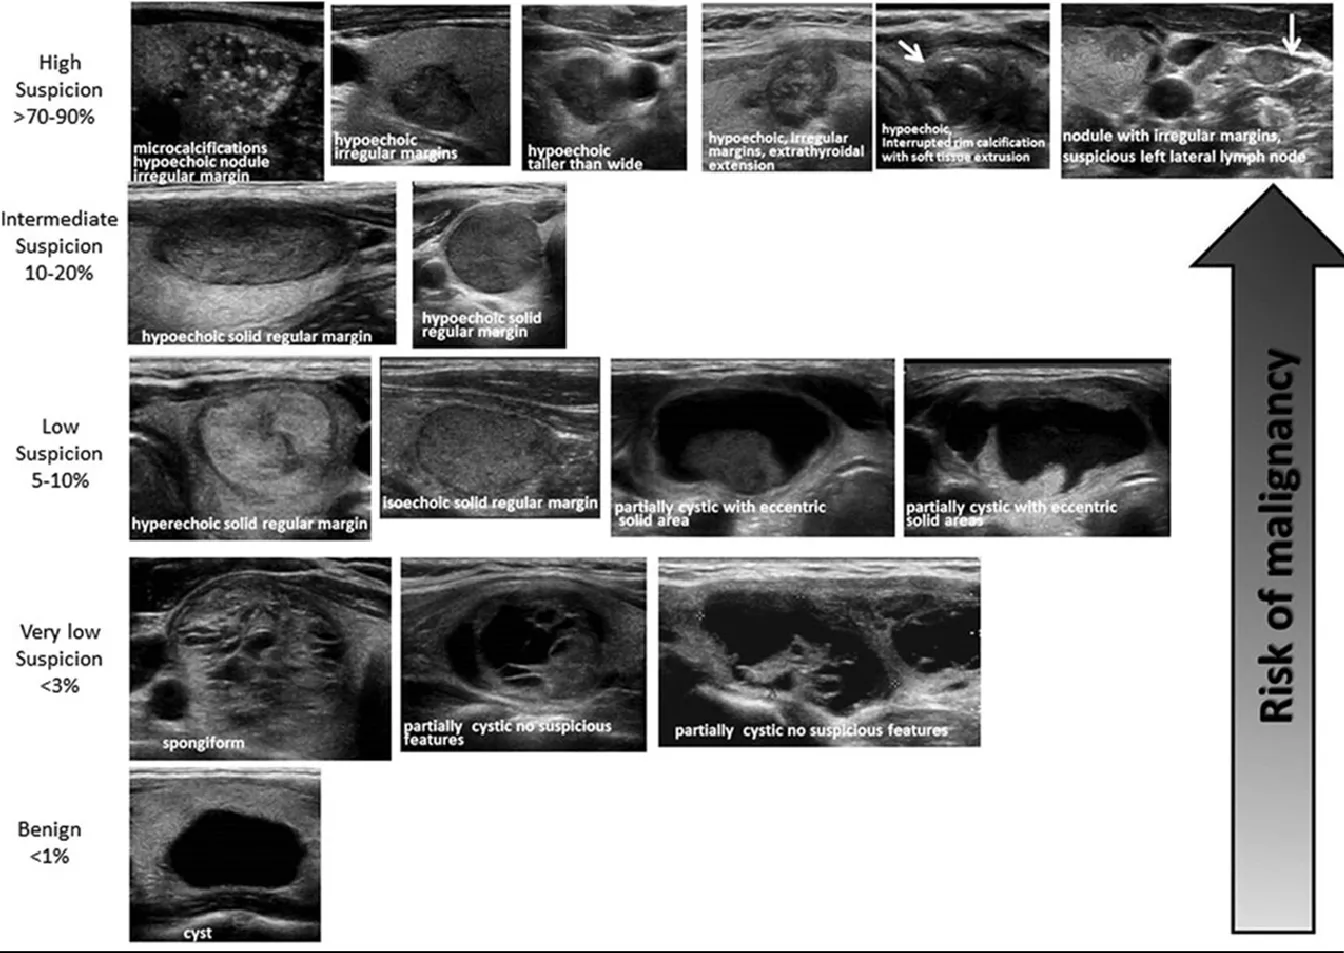

Hyperthyroidism

Goiter/MNG